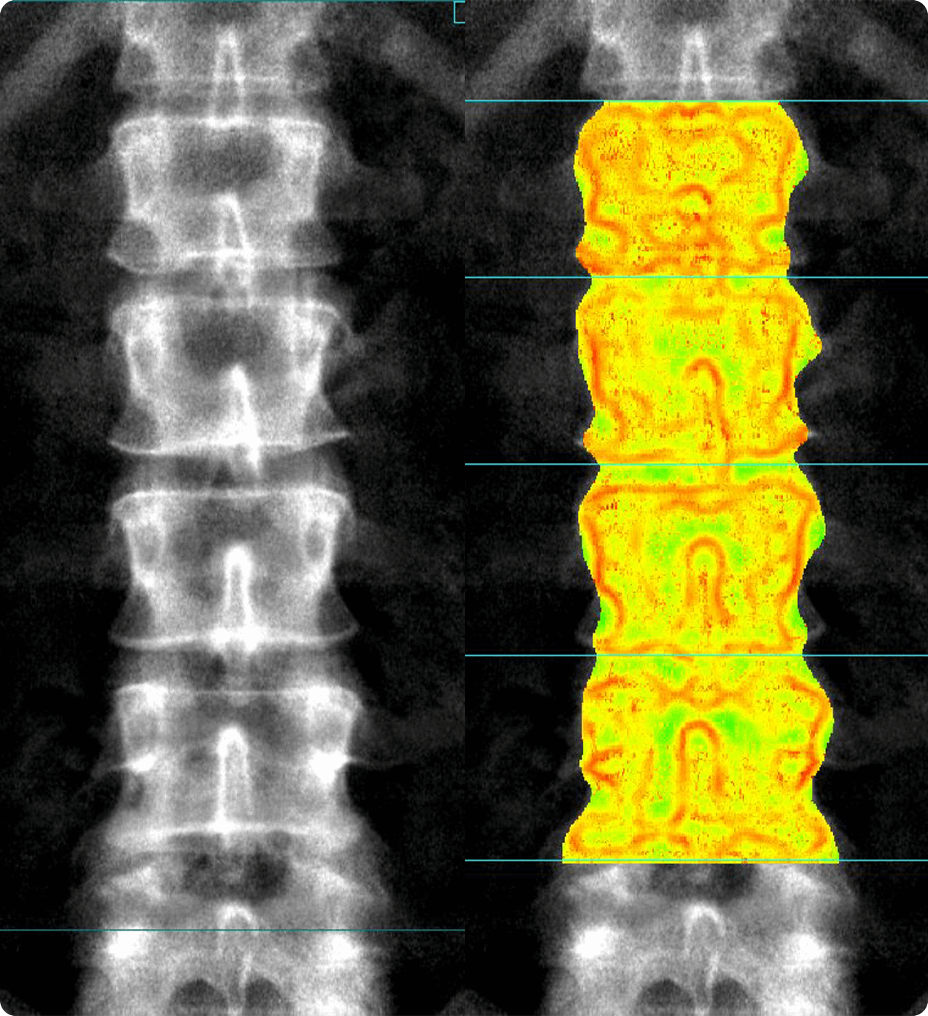

En el corazón de Revolution Advance se encuentra una cadena de adquisición de imágenes confiable y de alto rendimiento con 42 kW de potencia del generador, un tubo de rayos X de 3,5 MHU y detectores integrados que reducen la relación señal/ruido en un 20 %2. Esto va de la mano con nuestras aplicaciones inteligentes de reconstrucción de reducción de dosis, como ASiR2, que pueden proporcionar una dosis hasta un 40 % menor mientras se mantiene una alta calidad de imagen2.

En lo que respecta a la adquisición de imágenes de casos más desafiantes, como pacientes neurológicos, oncológicos o pediátricos, VISR3 (del inglés Volumetric Image Space Reconstruction, reconstrucción volumétrica del espacio de la imagen) reduce el ruido sin afectar la resolución de la imagen. Esto significa menos dosis para el paciente, a la vez que se mantiene la alta calidad de imagen que se necesita para diagnósticos más exactos.